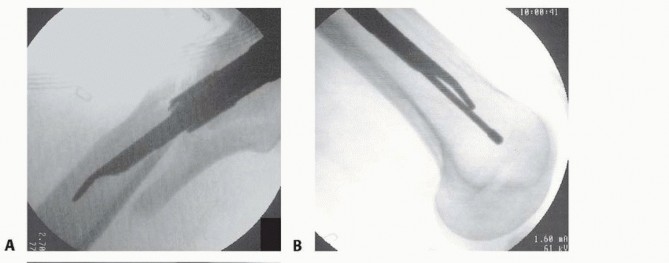

Short nails have distal locking capability, usually in a static or dynamic mode with most modern designs. I prefer dynamic locking. Most systems have this hole targeted through the proximal nail guide, and a single bicortical screw is usually sufficient. Long nails have distal locking capability with either static holes or a combination of static and dynamic. For length-stable proximal fractures, one bicortical screw is sufficient in a dynamic mode. Conversely, for segmental fractures or extensive comminution, two screws may be preferred. Distal interlocking is most commonly done using the same freehand technique used in the conventional femoral interlocking nail technique ( TECH FIG 8).

TECH FIG 8 • Distal freehand technique for long nails.